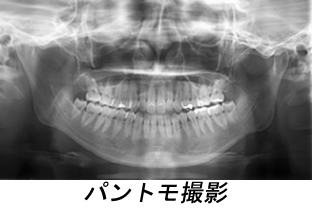

歯科領域撮影

口腔内の撮影であるパントモ撮影や、顎関節規格撮影を行っています。またセファロ

撮影といわれる頭部規格撮影を行い、睡眠時無呼吸症候群の診断に使われています。